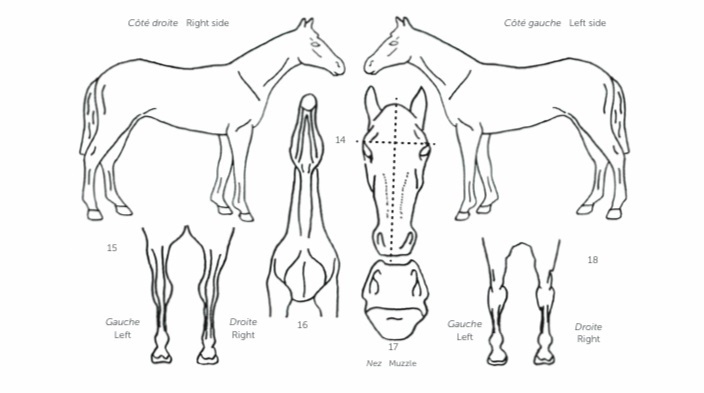

Volledige radiografische screenings kunnen uitgevoerd worden vanaf de leeftijd van 18 maand. De standaardkeuring bestaat uit 18 foto's waarbij de meest frequente aandoeningen van de ledematen kunnen opgespoord worden. Voor een uitgebreider pakket kunnen altijd bijkomende opnamen besproken worden.

Wij chippen en schetsen uw veulen, helpen u met het inschrijven bij het gewenste stamboek en het aanvragen van het paspoort.